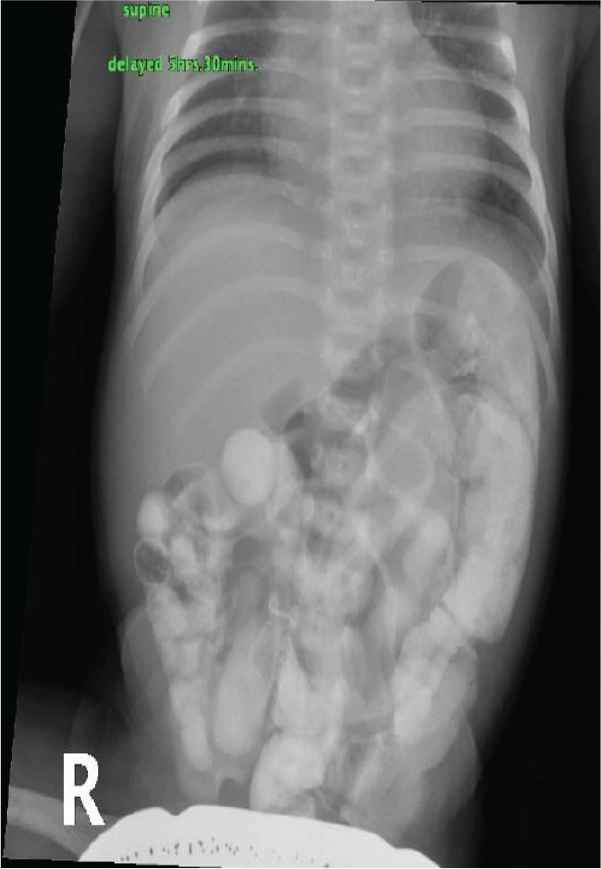

A full-term male with an unremarkable antenatal and perinatal history admitted on the date of birth to the Neonatal Intensive Care Unit (NICU) because of transient tachypnea of the newborn. During his stay, he developed episodes of hypoglycemia and intermittent yellow to green vomiting. There were no significant findings in the abdominal Ultrasound (US) and X-ray. He was discharged against medical advice as requested by the mother on the 3rd day of life. The baby stayed at home for 4 days with a history of intermittent vomiting. He was later readmitted to the NICU because of recurrent bilious vomiting and clinical jaundice on the 7th day of life. During his stay, he developed episodes of hypoglycemia and received phototherapy for prolonged jaundice and was kept Nill per oral (NPO) initially. Trials to resume feeding were always associated with intermittent vomiting, which was sometimes bilious or fecal. The result of abdominal examination was unremarkable. Interestingly, there was no distension, and the baby passed stool frequently. All workup to rule out sepsis, including metabolic disorders, were benign. Moreover, imaging studies, including abdominal US, X-ray, and upper and lower gastrointestinal tract contrast study (Figures 1–6, respectively), all revealed nonsignificant findings. Eventually, an explorative laparotomy was performed on the 17th day of life, which showed ileal stenosis (Figure 7), 32 cm from the ileocecal valve. The stenotic area was resected, and end-to-end anastomosis was carried out. Feeding was slowly started on the 5th postoperative day. He gradually reached full feeding with no vomiting and was discharged home on the 27th day of life and has been well since then.

Barium meal, supine – 5 h.

In congenital intestinal atresia, radiographic examination of the abdomen with X-ray and contrast studies is a useful diagnostic tool. For proximal jejunal and ileal atresia, the presence of a few dilated proximal bowel loops with no distal gas is observed. Intraperitoneal calcification can be seen in prenatal bowel perforation or meconium peritonitis [6]. Malrotation is ruled out using an upper gastrointestinal series contrast study. A contrast enema is used to reveal the atypical appearance of the colon, as may be seen in meconium ileus or Hirschsprung disease. If the contrast passes into the dilated loop of bowel, then atresia is ruled out. Ileal stenosis can be distal or proximal; in the case of proximal ileal involvement, the colon is usually normal in size as sufficient succus entericus reaches the colon from the small bowel distal to the obstruction as in our case; however, in distal involvement, it is generally unused and microcolon less than 1 cm in diameter is seen. Thus, clinicians should always consider the possibility of congenital intestinal stenosis in any newborn with unexplained vomiting even if the radiological data are not significant. The prognosis is excellent if treated with surgery.